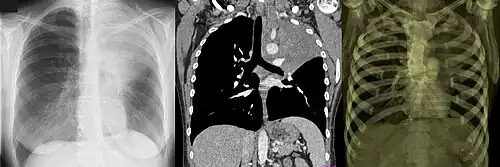

Digital rekonstruiertes Röntgenbild

Digital rekonstruierte Röntgenbilder (Abk.: DRR) werden im Rahmen einer modernen Strahlentherapie angefertigt. Sie ähneln normalen Röntgenbildern, stammen aber aus den Bilddaten einer Computertomographie. Im Computer wird eine virtuelle Sicht auf den dreidimensionalen Datensatz z. B. des Brustkorbes errechnet, wobei die Voxel eine dichteabhängige Transparenz erhalten. Das Ergebnis ist ein Summationsbild aller in Blickrichtung gelegenen Strukturen. Häufigster Zweck ist die Darstellung eines Strahlenfeldes aus Sicht der Strahlenquelle, das z. B. mit dem Simulatorbild verglichen werden kann.

Verschiedenen Darstellungsmöglichkeiten

- Kontrasterzeugung zwischen Weichteilgewebe und Knochen

- Kontrasterzeugung zwischen Weichteilgewebe und Lunge

- MIP (Maximumintensitätsprojektion)

- gleiche Gewichtung aller Dichtewerte